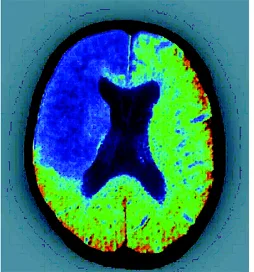

Prevenire l’ictus e le malattie cardiovascolari? Si può, partendo da una sana alimentazione e privilegiando alimenti ricchi di magnesio come verdure fresche a foglia verde, legumi, cereali integrali, banane e frutta secca. Secondo Susanna Larsson, coordinatrice dell’indagine condotta dal Karolinska Institutet di Stoccolma e pubblicata a gennaio sull’American Journal of clinical Nutrition, l’assunzione di magnesio nella dieta sarebbe infatti inversamente associata al rischio di ictus, in particolare di ictus ischemico (quello, cioè, causato da un coagulo di sangue che ostruisce il vaso sanguigno impedendo al sangue di fluire).